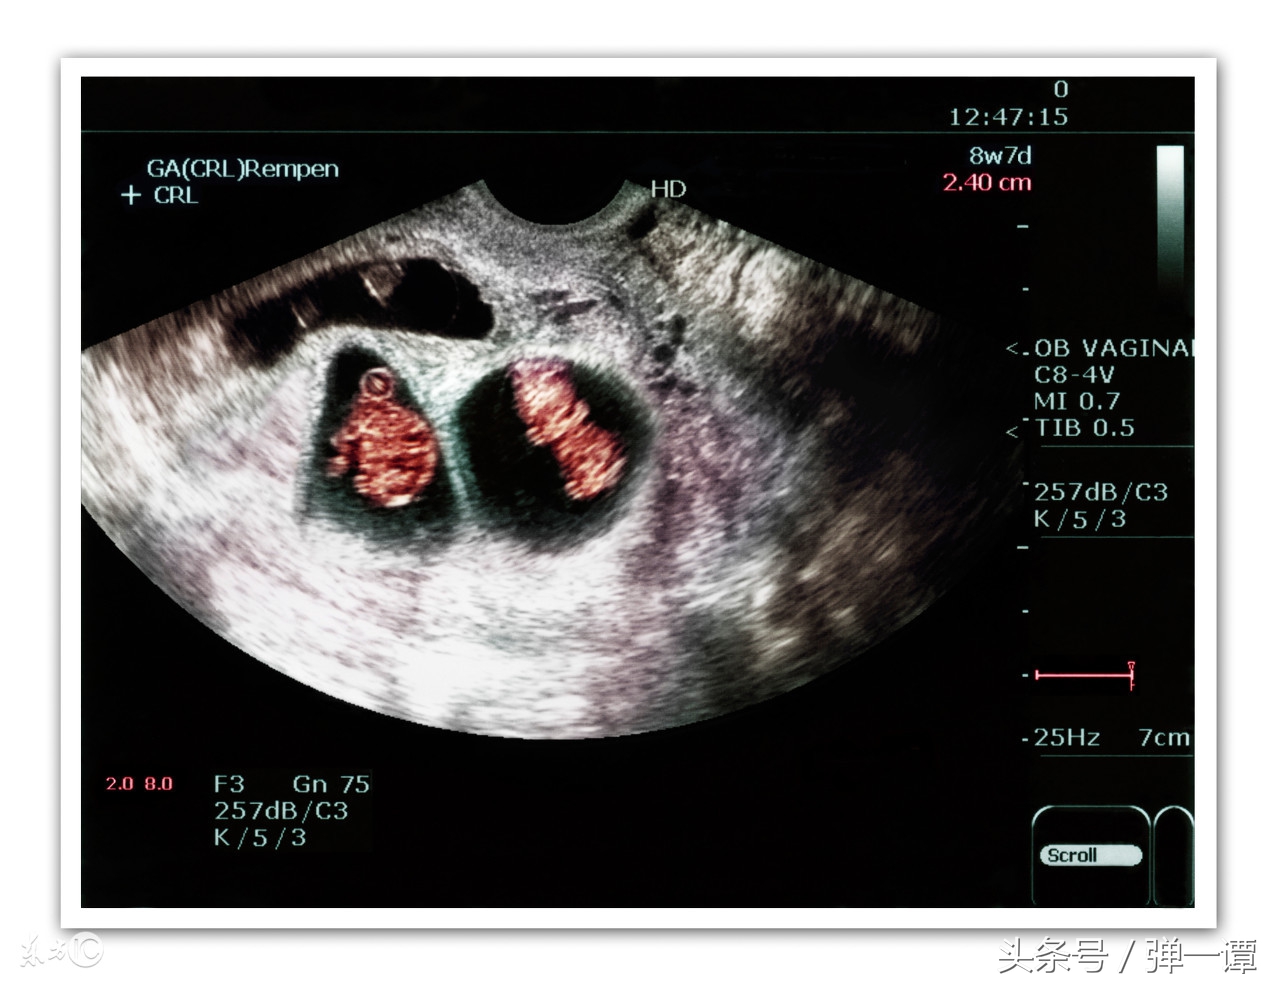

事实是,丹丹再次怀孕了,已经快三个月了,按照这么算,宝宝还没满月,她就怀上了,大夫告诉她这次是双胎,听到大夫的话,瞬间夫妻二人都愣了,哺乳期也能怀孕?大夫回答:母乳喂养期间,不来大姨妈并不意味着不排卵,如果期间*生活性**没有做好避孕措施的话,是有可能会怀孕的。

大夫也很疑惑问道:你的奶水没有比原来少么?肚子大了你没感觉啊?丹丹说:奶水少了,我婆婆就给孩子添加了奶粉,至于肚子,我以为是胖的,如果没有吐,或者肚子咕咕叫,自己还不知道呢!